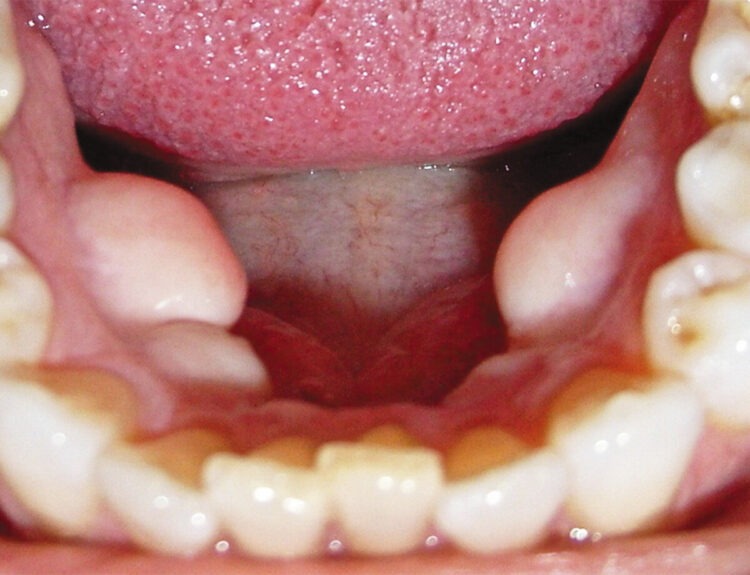

Sleep Apnea is a sleeping disorder that affects male and female population of any age. Adult males are mostly involved. Patients with nasal blockage, enlarged tonsils, a low-hanging soft palate, or a small jaw with an overbite are more likely to experience this disorder.

It may be of various types but Obstructive Sleep Apnea is the most commonly occurring one. It occurs when throat muscles interruptedly relax and block airway during sleep. Individuals having sleep apnea have multiple extended delays in their breath during sleep. These temporary breathing intervals cause low-quality sleep and adversely affect Oygen supply of the body. Loud snoring is the most noticeable sign of obstructive type.

A dentist in conjunction with a sleep specialist can help the patient in managing it using oral appliances. A practicing dentist has three options to treat the obstructive sleep apnea including mandibular advancement device, mouth guard, Tongue-retaining device.

Mandibular advancement device is an amazing plastic device which snaps over the patient’s upper and lower teeth. It works by temporarily moving the jaw forward, which reduces throat constriction and prevents snoring and sleep apnea. Older age or obese patients should opt for other recommended treatment as this appliance show no efficacy in such cases.

Mouth guards are devices similar to mandibular advancement devices which help to reposition the lower jaw. However, its potential correction ability is lesser than mandibular advance device. Tongue-retaining device consists of a soft plastic splint placed around patient’s tongue. It holds the tongue forward and out of mouth throughout the night that makes mouth dry and causes discomfort.